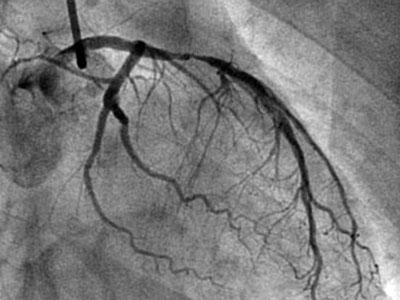

很多心脏病患者对于植入冠心病支架还是持有抵触的态度,即使造影提示血管狭窄了90%,医生建议支架手术。不少心脏病患者问过我,“如果冠状动脉狭窄90%,就是只吃药,不放支架会怎样?

心脏病的血管狭窄,一般是由于冠状动脉粥样硬化斑块发展到一定程度后发生破裂,血液中血小板在板块处聚集,血栓负荷加重导致。心脏病患者口服的药物,尤其是阿司匹林、氯吡格雷,会抑制血小板的聚集,从而控制狭窄的进展。

所以理想状态下,通过口服抗血小板药物能够维持血管狭窄程度不加重。但是这仅仅是理想状态,只有极少数患者才有可能出现。要知道冠心病患者存在众多诱发血管狭窄病变的因素,即使吃药效果好,多数狭窄病变依然会处于缓慢加重的状态。另外,当血管狭窄超过了90%,已经会严重影响冠状动脉供血,导致心肌供血不足出现心绞痛,甚至会进展为心肌梗死,为了病人的生命安全,医生断然不会允许病人药物保守治疗的。

很多心脏病患者口中都流传着某某患者坚持只吃药,不放支架,复查造影时居然血管狭窄减轻的传说。其实,我也见过类似病例,但是并不是血管狭窄90%这种严重情况。有的患者是弥漫性的血管病变,血管狭窄60%-75%左右,斑块不稳定,血栓负荷较重,通过口服抗血小板药物,复查造影时会因为斑块的稳定和血栓负荷的减轻出现影像学上的狭窄减轻。

但这仅仅是在造影这种二维图像上的表现,固有的狭窄病变往往并不会减轻。